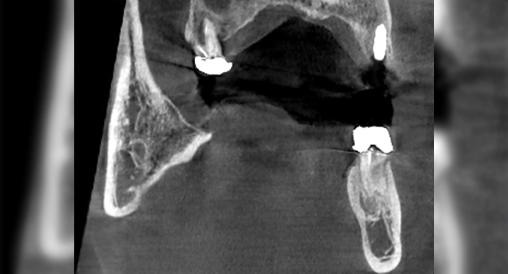

Технология уменьшения артефактов ART-V

Металлические предметы ухудшают визуализацию и снижают точность диагностики. Алгоритм для уменьшения влияния металлических артефактов снижает отражение рентгеновских лучей от плотных объектов, что повышает качество диагностики.

ART-V Off

ART-V On